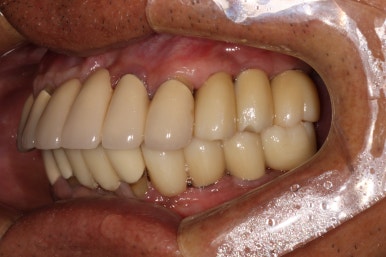

우측 어금니를 보시면, 너무나 많은 치석으로 인해 만성치주염에 시달렸던 치아들은 사라지고, 이제 깔끔하게 임플란트로 대체된 것을 보실 수 있습니다.

임플란트는 보통 1 piece로 제작되기 때문에, 기존에 흔들리고 잇몸이 올라가버린 어금니보다 오히려 음식도 덜 끼고.. 사용하기 상당히 좋은 환경이 조성되었지요.

좌측 어금니 또한 깔끔하게 그럴싸하게!! 본인치아와 흡사한 형태로 제작해드렸습니다.

사실 처음에 잇몸 염증으로 고름이 가득 차있던 왼쪽 아래 송곳니 부위에는 임플란트 심는 것 자체가 불가능 했습니다만, 인접한 자리에 임플란트를 심어내어 마치 임플란트가 있는 것 같이 깔끔하게 제작 완료!